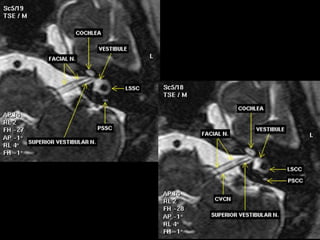

IAC MRI Anatomy and Search Pattern :

The IAC is divided superiorly and inferiorly by a bony lamina (falciform crest):

- Smaller superior part: - Larger Inferior part:

- Superior vestibular n. - Inferior vestibular n.

- Facial n - Cochlear n.

Bill’s Bar divides the superior portion of the canal anterior to posterior

Falciform crest